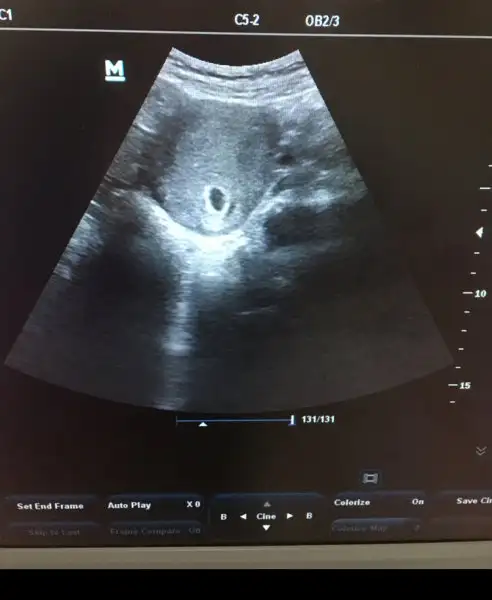

Doktordan geliyorum 6+2 bebek gözüktü ama kalp atısını göremedi dr gec döllenmeye baglı olabilir dedi haftaya cuma yine cagırdı ama moralim sıfır neden görmedi acaba diye

Bende dün 6+4te bebeği gördük ama kalp atışını göremedik canım daha erken 9.haftada gören bile var

Karindanmi vajinal mi baktı. Ayrica senin gibi ayni gunlerde duyamayan cok arkadas var burada bencr moralini bozma bir gun bile cok farkettiriyor. İlla duyulmasi sart değildi icini ferah tut.

Canim ben 5+3 keseyi gördük daha cok küçüktü 2hafta sonra gel dedi bugun gittik yani 7+3 duyduk kalp atisini. Daha erken annesi sabret 1hafta sonra duyarsin insallah kalp atışını

Gözün aydın canım. Amaneden sıfır moralin birçok kişi 7. Haftayı doldurduktan sonra duyuyor kalp atışını. Öyle düşünme bebişini üzme canım.

Kizlar cok sukur kesemizi gorduk, doktor hersey yolunda, hersey olmasi gerektigi gibi dedi rahatladim. 5 hafta sonra yine gel dedi daha erken gelmene gerek yok, hersey yolunda.

Kızlar üzmeyelim bebekleri inşaallah yakında kalp atışlarını da duyacağız. Her çocuk nasıl farklıysa her hamilelik ve embriyo da farklı. Sabredelim inşaallah maksimum 2 haftaya duyacağız, ben de bugün gittim sadece bebek gözüktü kalp atışına bakmadı bile